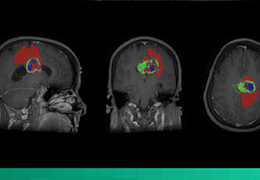

成像智能。

Eclipse 成像智能功能提供强大的处理能力和最佳质量的影像,同时减少质量错误并提高剂量效率。

凭借 AI、专有算法和先进的影像处理能力,提供出色的影像质量和无与伦比的诊断信心。